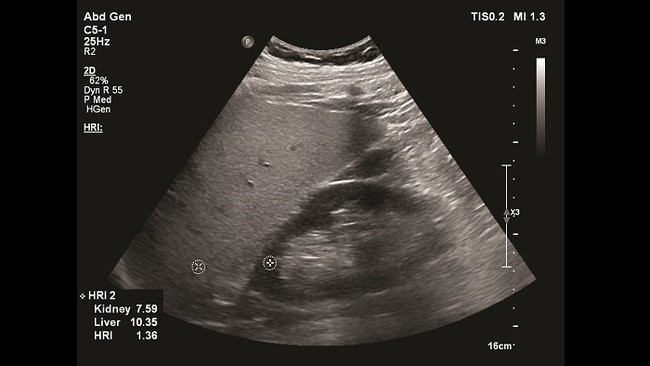

Hepatorenal Index(肝腎インデックス)

肝臓に脂肪が蓄積すると,隣接する腎臓と比較して肝臓のエコー輝度が上昇することは「肝腎コントラスト」として一般的によく知られているが,主観的な評価方法であることが問題であった。Hepatorenal Index (HRI)では肝臓と腎臓それぞれの輝度を装置上のゲインやグレーマップ,ダイナミックレンジなど画像調整を除した上で数値化して比率を計算するため,客観的な肝腎コントラストの評価が可能となる。